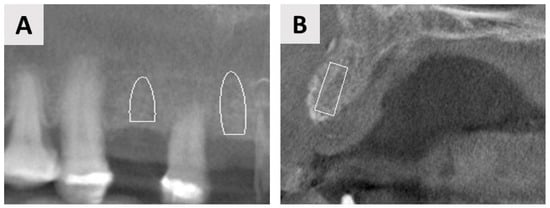

3. Case Report One: GBR with Delayed Implant Placement